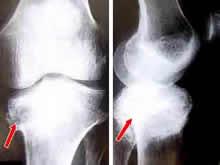

神经性关节病是由Charcot于1868年首先描述指出的发病于关节神经部位的疾病,故也称为charcot关节病,即夏科氏关节病。此类疾病为无痛觉所引起,又有无痛性关节病之称。是一种继发于神经感觉和神经营养障碍的破坏性关节疾病,常见于40~60岁,男女比例为3∶1。